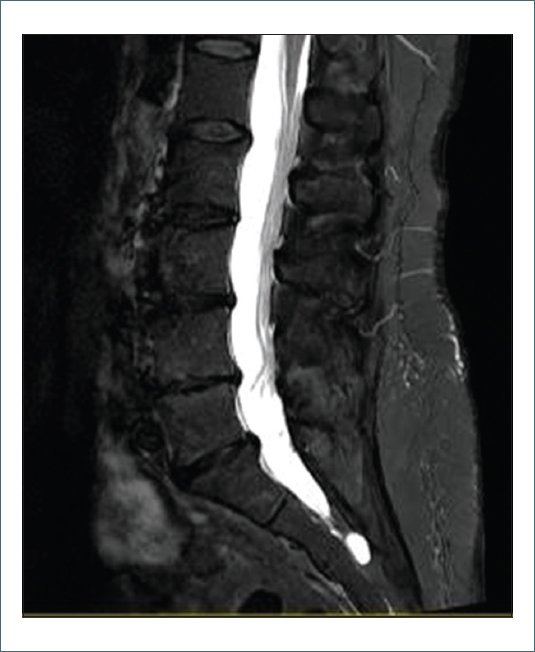

En cuanto al tratamiento, se descartó realizar una epidural caudal por el posible riesgo de punción del quiste de Tarlov y se optó por una infiltración transforaminal de la raíz de S1 derecha (Fig. 2) con 8 mg de dexametasona y 1 mg de lidocaína 0,2% (en total 1,5 ml) bajo control radiográfico.

Figura 2. Infiltración transforaminal de la raíz S1 derecha.

Por lo que se refiere al tratamiento, debido a la ineficacia del tratamiento conservador farmacológico, se decidió realizar una técnica intervencionista. Con el diagnóstico de lumbociatalgia bilateral secundaria a la protrusión discal de L5-S1 la primera opción terapéutica sería una infiltración epidural vía caudal. Es una técnica con una tasa de complicaciones baja pero aun así, se deben tener en cuenta las variaciones anatómicas como son los quistes de Tarlov y los posibles riesgos asociados, ya que se han reportado casos de punciones durales inadvertidas con bloqueo motor posterior, de distribución errática de los fármacos o también un aumento del riesgo de provocar una compresión nerviosa por el volumen de anestésico local administrado. Por todo ello, se optó por una infiltración transforaminal de la raíz nerviosa S1 derecha dado que la paciente presentaba dolor predominantemente en el lado derecho. Esta técnica nos permite administrar fármacos directamente en la raíz afectada y en este caso una menor tasa de complicaciones.